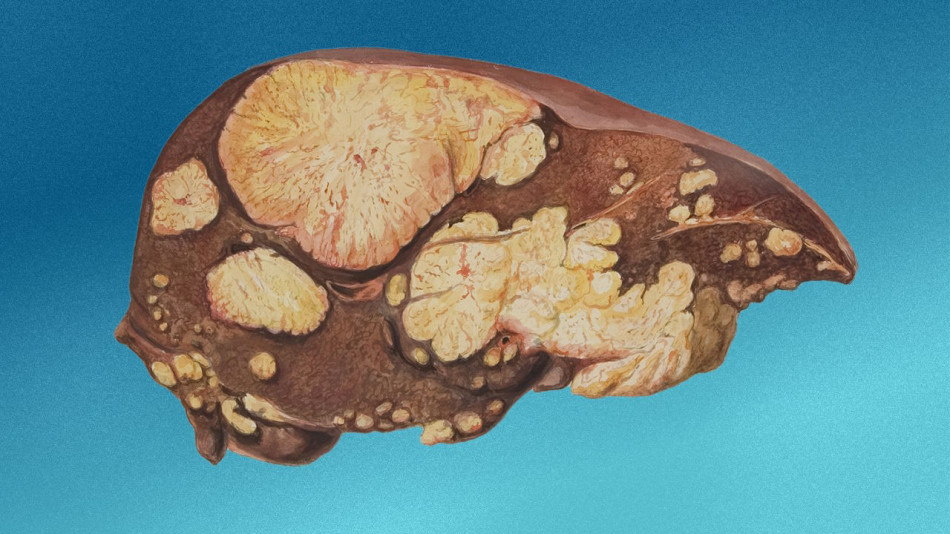

Лікарі взяли зразки тканин із пухлини та з’ясували, що чоловік мав дрібноклітинний рак легень, який складає приблизно 15 відсотків усіх випадків раку легень. Обстеження не виявило в пацієнта метастазів у мозку чи інших органах, тому хірурги вирішили видалити пухлину під час операції. Хоча спершу чоловік одужував повільно, а також йому довелося обмежити активність через видалення значної частини легені, пацієнт перебуває в ремісії.

Хоча вже відомі випадки, коли травми призводили до розвитку раку, досі дрібноклітинний рак легень пов’язували здебільшого з курінням. Тож випадок американця вказує на можливий зв’язок між цим видом раку та травмами, особливо з залученням металевих предметів, які можуть спричиняти надмірний ріст клітин і перетворення їх на ракові.